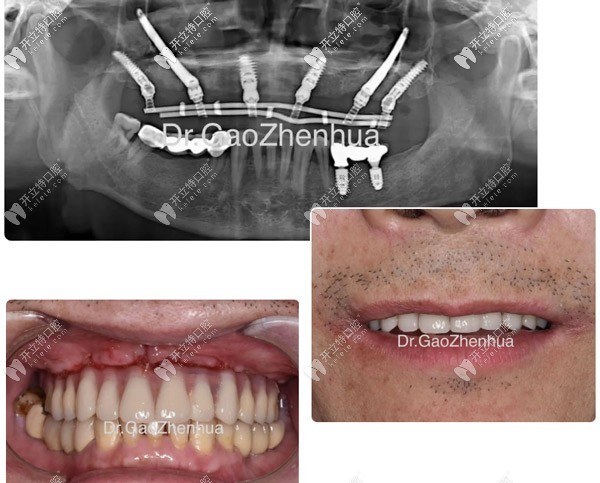

目前上海鼎植口腔中半口牙技術(shù)好的醫(yī)生有:黎強(qiáng)、高振華、謝正新、李君首、張永新等院長(zhǎng)。m.ardc-srvc.com

上海永博口腔門診部高振華

高振華

擅長(zhǎng):種植牙